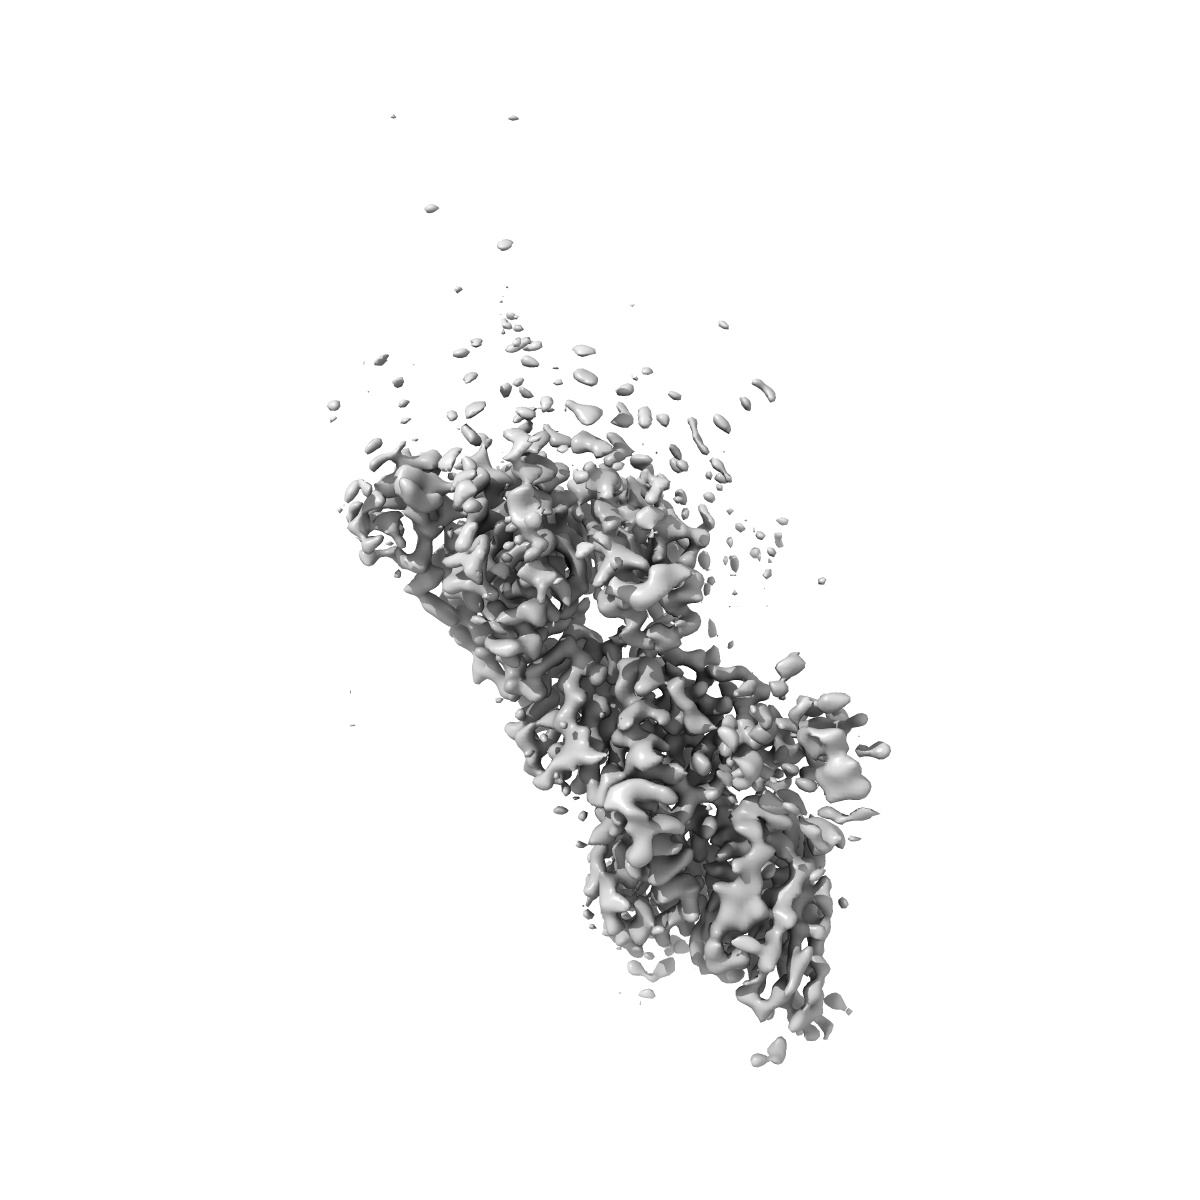

XBB-4 Fab in complex with SARS-CoV-2 BA.2.12.1 Spike Glycoprotein

Single-particle3.41 Å

Sample: XBB-4 Fab in complex with SARS-COV-2 BA.2.12.1 Spike Glycoprotein